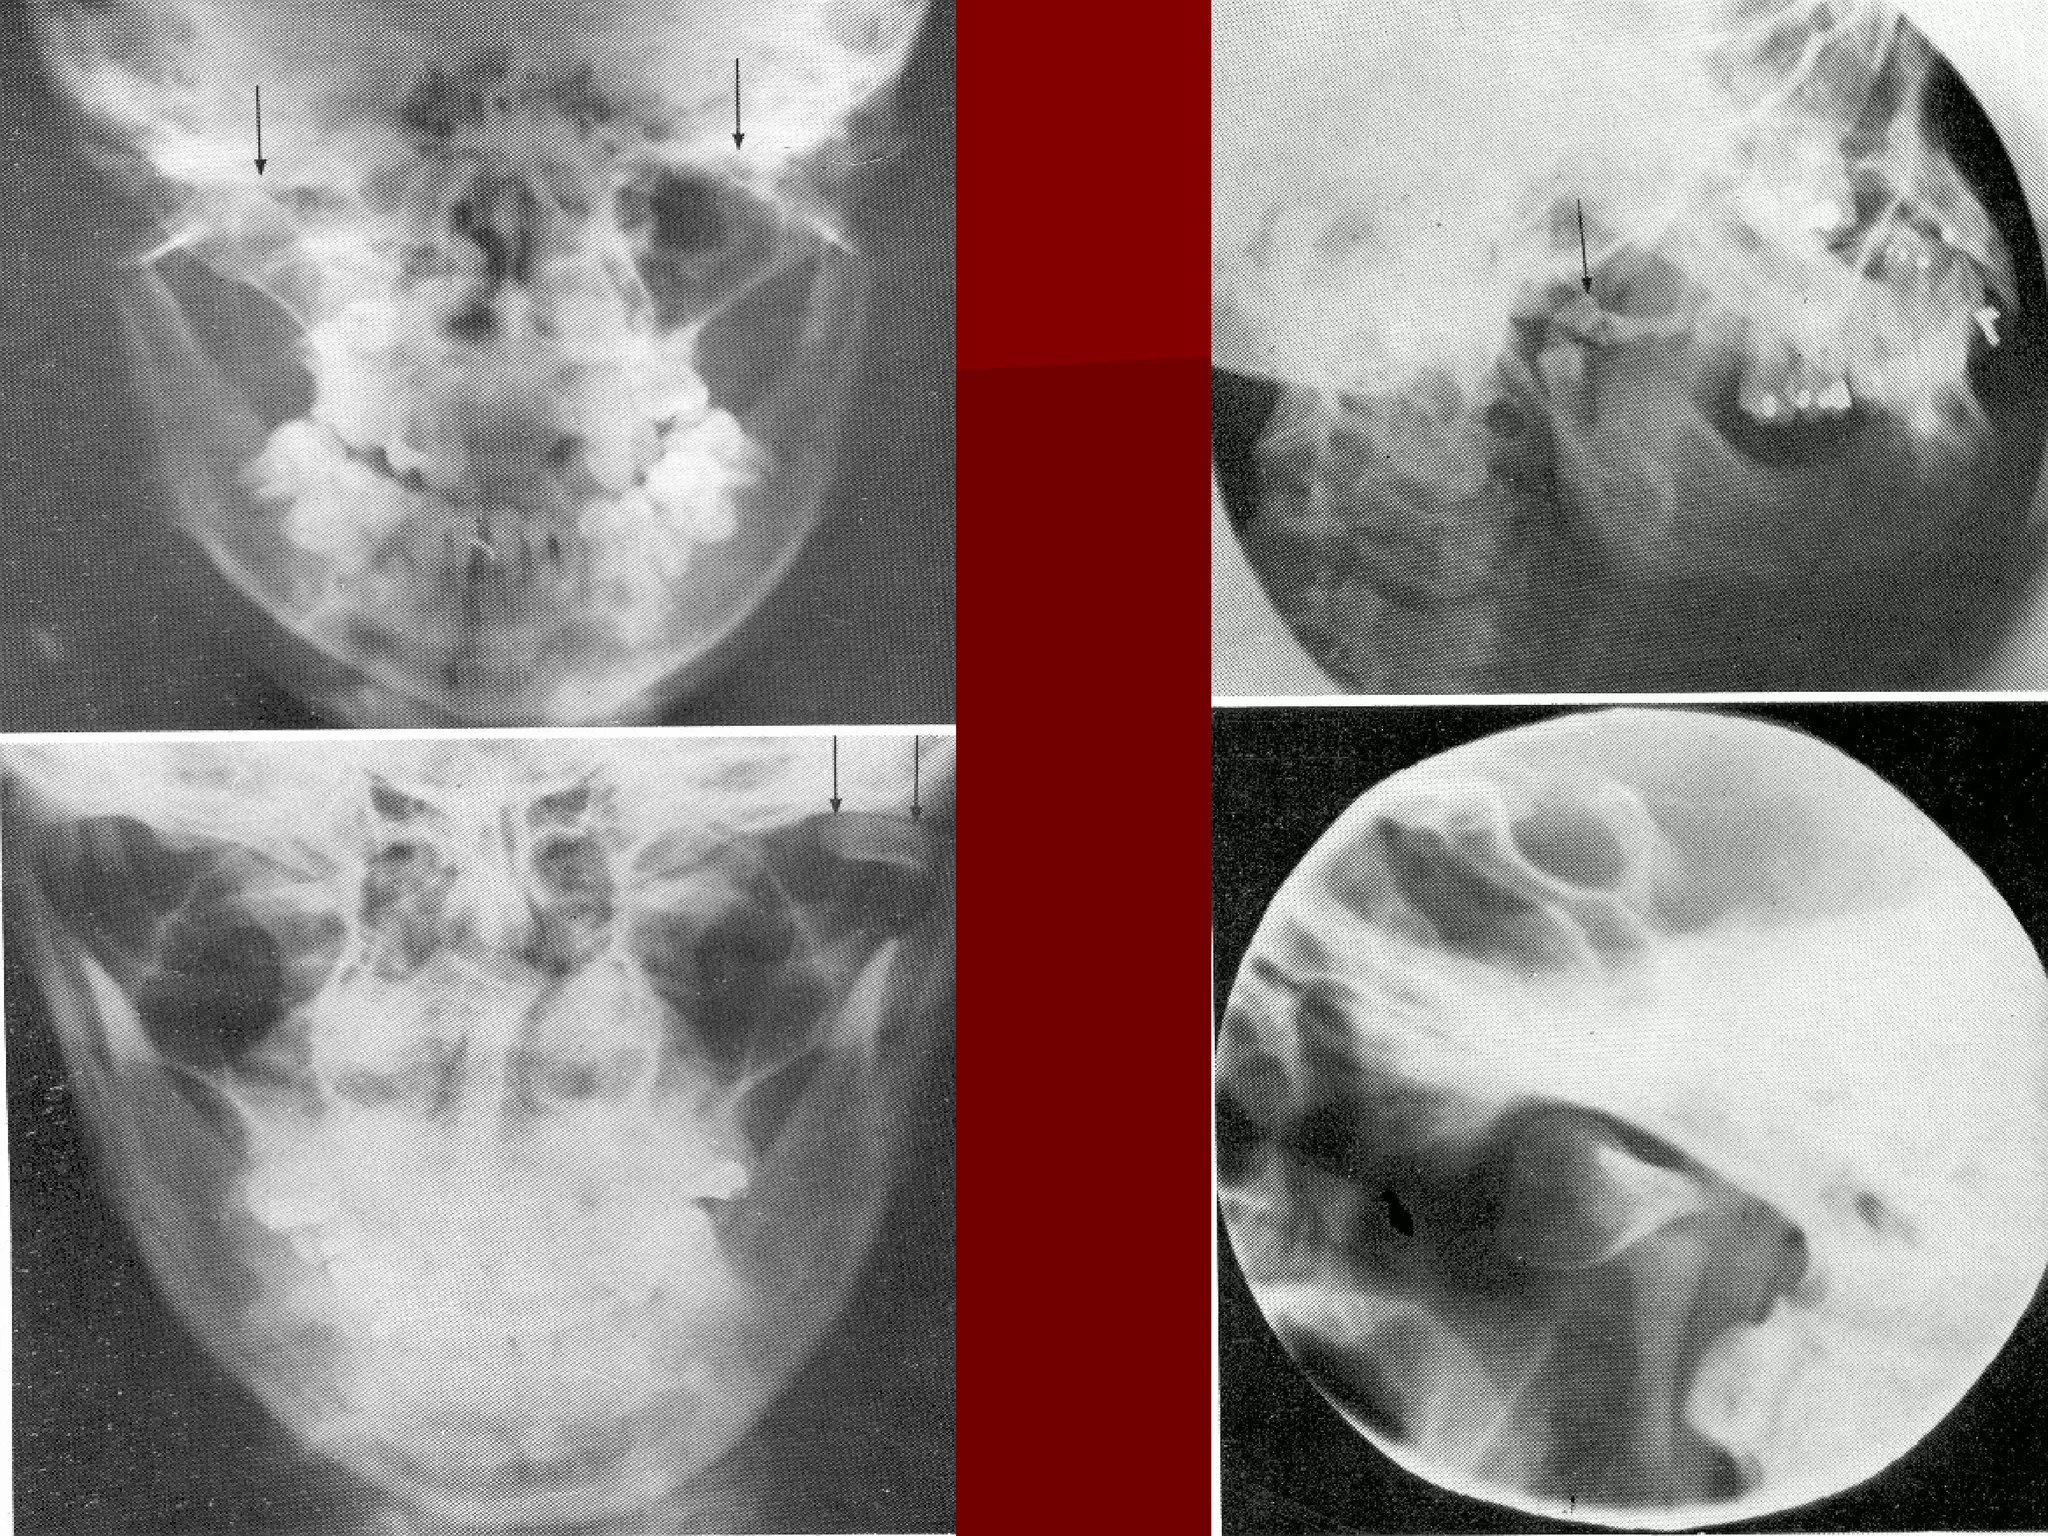

RRAADDIIOOGGRRAAPPHHSS && OOTTHHEERR

IINNVVEESSTTIIGGAATTIIOONNSS

 OOPPGG ((VViieeww ooff bbootthh ccoonnddyyllee))

 TTMMJJ VViieeww

– TTrraannss OOrrbbiittaall

– TTrraannss PPhhaarryynnggeeaall

 CCTT SSccaann:: IIff ddiissppllaacceedd ((oorr)) DDeevviiaatteedd

RRAADDIIOOGGRRAAPPHHSS && OOTTHHEERR IINNVVEESSTTIIGGAATTIIOONNSS  OOPPGG ((VViieeww ooff bbootthh ccoonnddyyllee))  TTMMJJ VViieeww – TTrraannss OOrrbbiittaall – TTrraannss PPhhaarryynnggeeaall  CCTT SSccaann:: IIff ddiissppllaacceedd ((oorr)) DDeevviiaatteedd